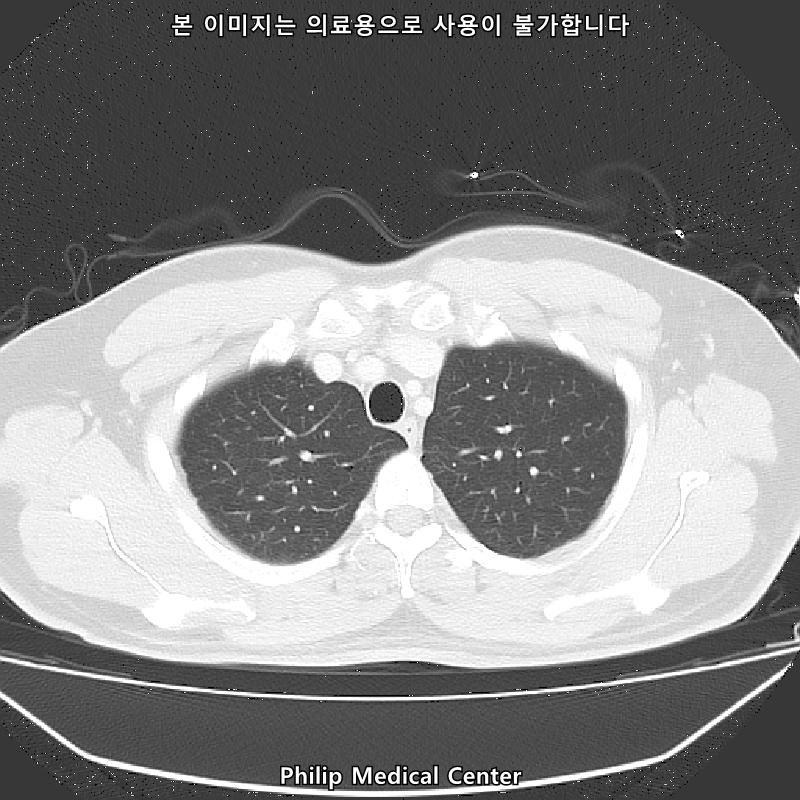

안녕하세요, 저선량 폐CT 검사결과 아래와 같이 나왔는데요, 어떤의미일까요ㅠㅜ

(우측 폐첨부에 경미한 섬유성변화와 우중엽에 약 3mm크기의 결절)

• 1번 째 사진

우측 폐첨부에 경미한 섬유성변화와 우중엽에 약 3mm크기의 결절이라는 것은 이상 소견이긴 하지만 보통 경과관찰을 하는 소견입니다.